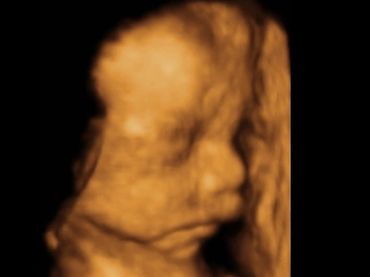

All our providers do their own ultrasounds in the office during your visit. We are known for our ultrasounds and do at least four with each pregnancy. And we can record your ultrasound on a USB device for you to take home and share!